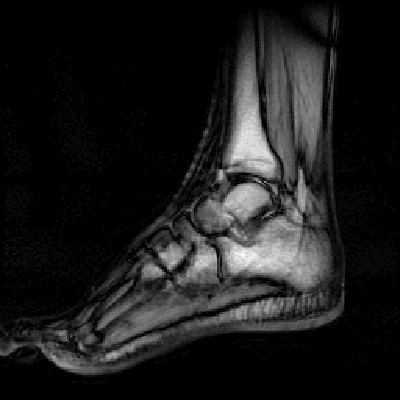

Shock wave therapy for recalcitrant plantar fasciitis with heel spur:

a prospective randomized placebo-controlled double-blind study